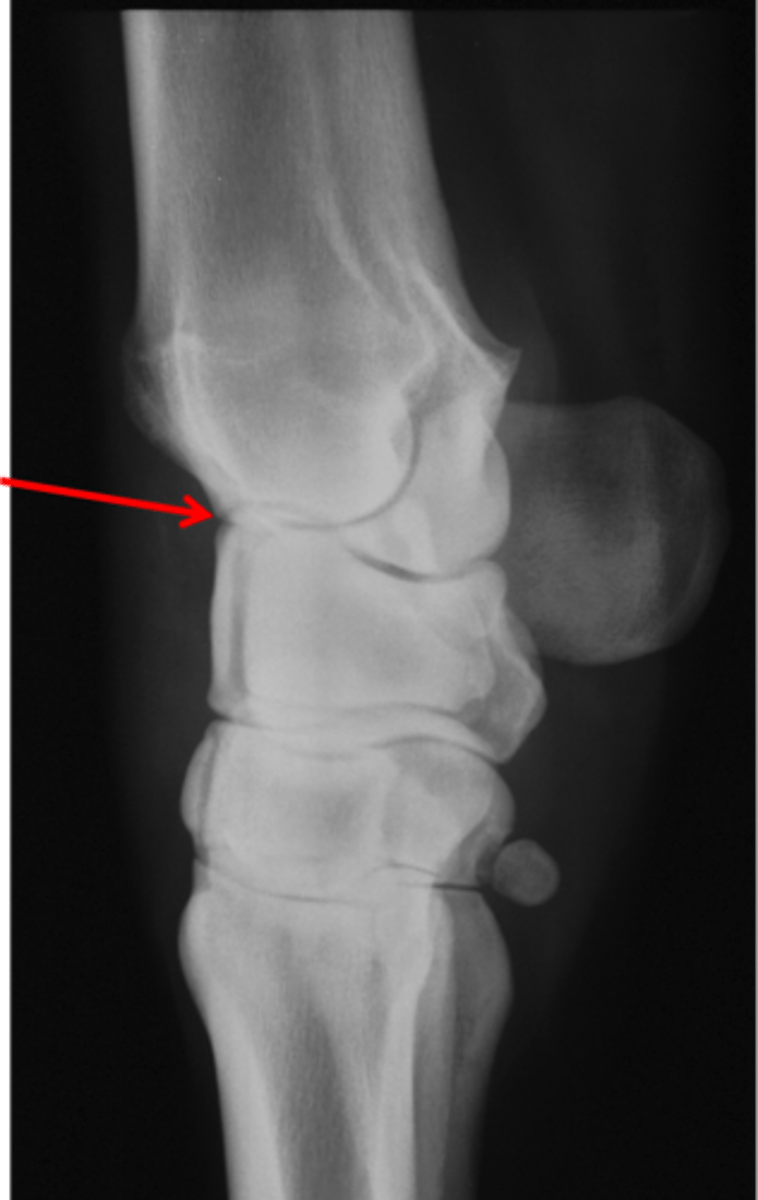

Pastern joint, LM

ID joint and view

Short pastern (P2)

Long pastern (P1)

Pastern joint (proximal interphalangeal joint)

Distal sesamoidean ligament

Long pastern (P1)

Short pastern (P2)